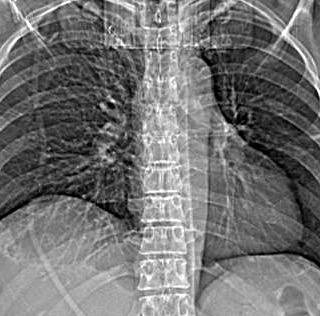

149. TORACOABDOMINAL: GANGLIOS

Líneas paraespinales formando un “paréntesis” por encima del diafragma. El signo señala el origen “intratorácico” de la lesión.

Conrad A et al. Pott’s disease associated with large and multiple abscesses in a 30-year-old migrant from Chad. BMJ Case Rep 2018

(lesiones toracoabdominales) La divergencia de las líneas paraespinales apunta a lesión toracoabdominal, que desde el tórax desciende y penetra en el abdomen.

Signo del “iceberg” positivo en Tb vertebral

Afectación por vía hematógena. Región dorsolumbar más frecuente. Afectación inicial: irregularidad de los platillos vertebrales, disminución del disco intervertebral con esclerosis ósea adyacente. Kim. Radiographics.2001